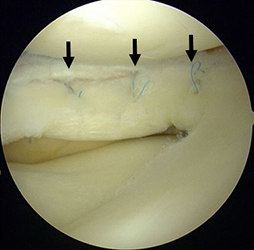

関節鏡視下半月板部分切除術・縫合術

本手術は内視鏡を用いて行うため、少数の小さい傷で低侵襲に行う事ができます。可及的に縫合し半月板の温存を試みますが、損傷形態によっては部分切除を選択します。

前方に逸脱した外側半月板を整復し縫合した